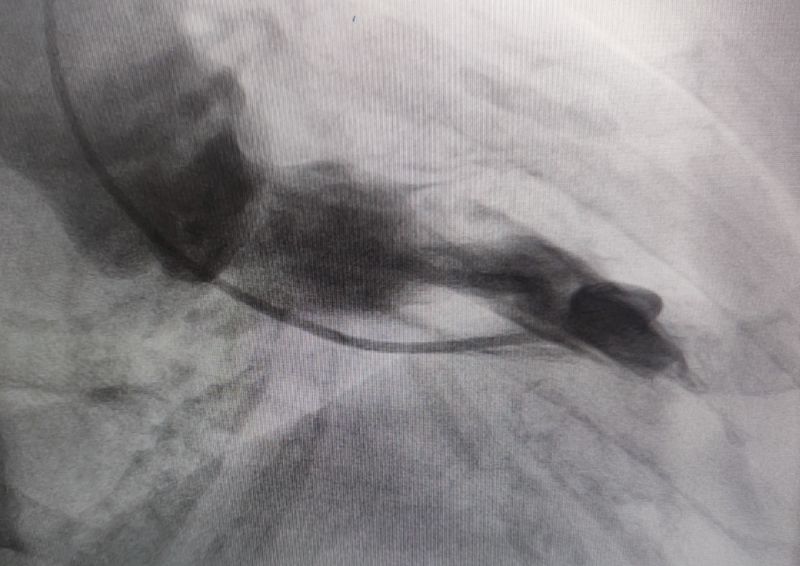

術(shù)前

面對(duì)這一復(fù)雜病情,崔旭輝主任醫(yī)師、馮韓章副主任醫(yī)師團(tuán)隊(duì)展開(kāi)了全面且深入的評(píng)估討論。經(jīng)審慎分析,最終確定室間隔化學(xué)消融術(shù)(PTSMA)為最佳治療方案。PTSMA是通過(guò)導(dǎo)管將無(wú)水乙醇精準(zhǔn)注入供應(yīng)肥厚室間隔的間隔支血管,利用化學(xué)作用使血管閉塞,促使肥厚的室間隔缺血、壞死、變薄,有效降低或消除室間隔心肌收縮力,從而拓寬心室流出道、緩解梗阻癥狀,顯著改善患者的臨床狀況。

經(jīng)過(guò)多輪嚴(yán)謹(jǐn)?shù)男g(shù)前討論,在吳棟梁院長(zhǎng)的專業(yè)指導(dǎo)下,崔旭輝主任醫(yī)師團(tuán)隊(duì)決定在臨時(shí)起搏器的安全保護(hù)下,為患者實(shí)施冠狀動(dòng)脈造影術(shù)及室間隔化學(xué)消融術(shù)。術(shù)中,團(tuán)隊(duì)通過(guò)造影精準(zhǔn)鎖定第一穿隔支為消融靶血管。測(cè)壓數(shù)據(jù)顯示:左室壓260/15mmHg,流出道173/6mmHg,主動(dòng)脈壓106/70 mmHg,壓力階差達(dá)87mmHg。隨后,團(tuán)隊(duì)使用2.0X15mm預(yù)擴(kuò)球囊以8atm壓力阻斷第一穿隔支遠(yuǎn)端血流1分鐘,再次測(cè)壓時(shí),壓力從269/7mmHg驟降至174/4mmHg,這一結(jié)果充分證實(shí)該血管正是室間隔的有效供血血管。緊接著,團(tuán)隊(duì)通過(guò)SPRINTER OTW2.0×8mm球囊緩慢注入1.4ml無(wú)水酒精。10分鐘后復(fù)測(cè),左心室壓降至136/5 mmHg,主動(dòng)脈壓為112/93 mmHg。術(shù)后第2天,王女士胸悶、氣短、心悸等不適癥狀完全消失。復(fù)查心臟彩超顯示:EF值與FS值保持穩(wěn)定,收縮期左室流出道血流速度降至252cm/s,PG值為25mmHg。